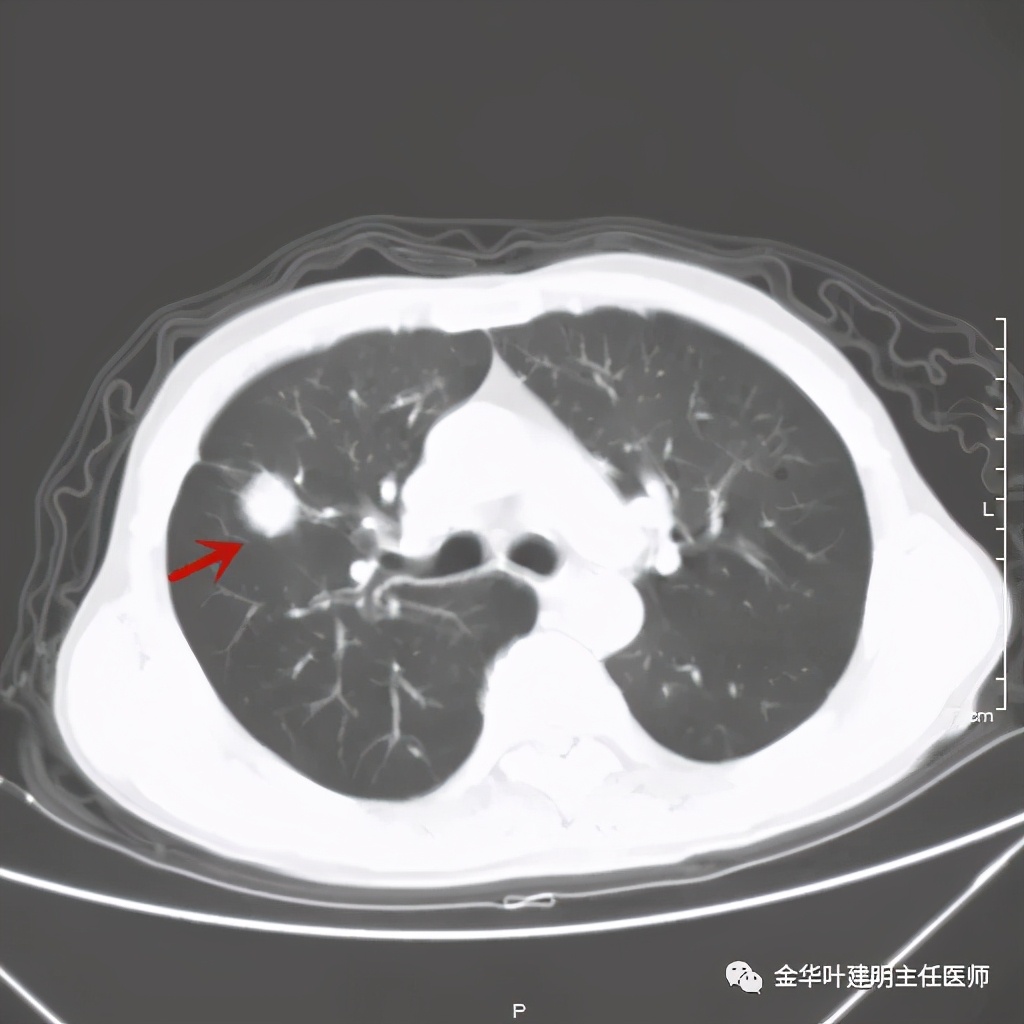

金华的某A,今年73岁,男性。检查发现右上肺占位,肿瘤筛查指标正常,血常规与CRP正常,临床有反复咳嗽、咳痰2年余(考虑慢支的关系,近期也许同时有病灶的影响)。一年前还在外院做过支气管镜,也未见确切异常。我们先来看他这次的胸部CT图像:

上图示病灶